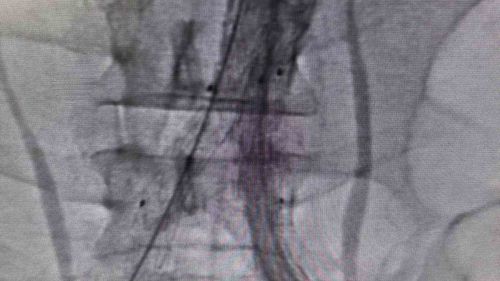

Bilecik'te Kapalı Yöntemle Hayat Kurtaran Ana Atardamar Onarımı

Bilecik'te 39 yaşındaki Mehmet D.'nin ana atardamarındaki yırtık kapalı yöntemle stentle onarıldı; hasta ağrıları geçerek sağlıklı şekilde taburcu edildi.

Bilecik'te kapalı yöntemle hayat kurtaran onarım39 yaşındaki Mehmet D., şiddetli sırt ve karın ağrısı şikâyetiyle başvurdu. Daha önce farklı sağlık kuruluşlarına başvurduğu ancak net tanı konulamadığı ifade edilen hasta, Bilecik Eğitim ve Araştırma Hastanesi acil servisinde yapılan ileri görüntüleme tetkikleriyle…